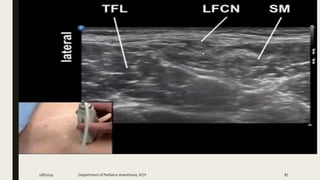

TAP BLOCK

2/8/2019 Department of PediatricAnesthesia, KCH 91